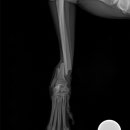

• 24시 에피소드 동물 메디컬 센터 | 만촌동 동물병원 강아지 요골·척골 골절 수술 후기 [24시에피소드동물메디컬센터]

만촌동 동물병원 강아지 요골·척골 골절 수술 후기 [24시에피소드동물메디컬센터] 만촌동 동물병원 ​ 안녕하세요. ​ 풍부한 경험과 따듯한 진료를 바탕으로, 반려동물의 건강하고 행복한 하루하루를 함께 만들어 가는 만촌동 동물병원 24시에피소드동물메디컬센터 입니다. 24시에피소드동물메디컬센터 대구광역시 동구...

에피소드동물메디컬센터(2025-06-26 12:41:00)